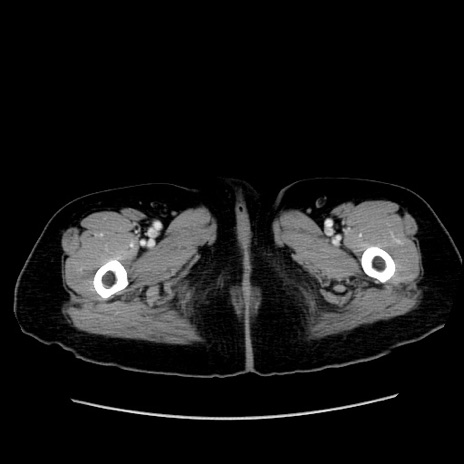

冠状断像

【症例】80歳代女性

【主訴】下腹部痛

【現病歴】約8時間前より下腹部痛の出現あり、救急外来受診。

【既往歴】両側付属器切除

【身体所見】意識清明、下腹部正中に手術痕あり、その部位に一致して圧痛と反跳痛あり。腸蠕動音は亢進。

【データ】WBC 9300、CRP 0.15